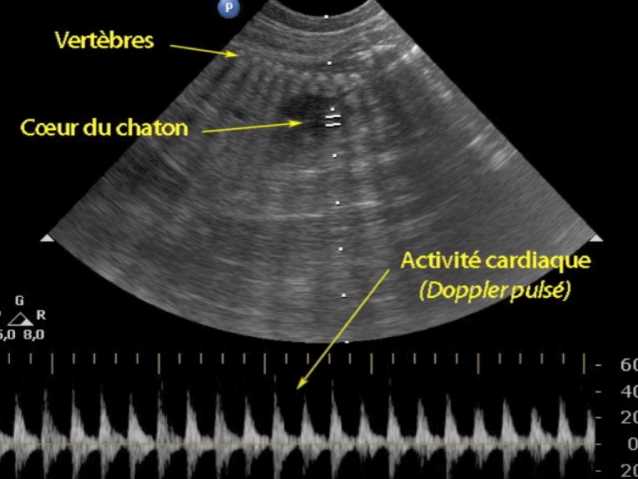

Les premières images de cette vidéo présentent des radiographies d'une chatte gestante qui permettent de reconnaître les squelettes des chatons à venir, ce qui rend leur comptage assez facile. Cependant, pour connaître leur vitalité, on préfère l'échographie qui, grâce au Doppler notamment, permet l'observation fine des battements cardiaques ainsi que la mise en évidence des flux sanguins.